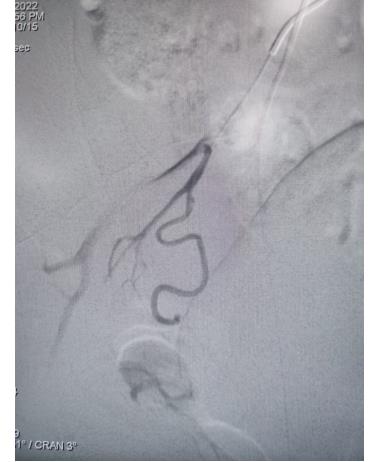

冠脈手術(shù)前

51歲的郭女士,因反復(fù)胸痛3天,加重2小時(shí)入院,入院后胸痛癥狀反復(fù)發(fā)作,檢查心電圖提示前壁導(dǎo)聯(lián)ST段明顯壓低,在此危急時(shí)刻心九科值班醫(yī)生陶醫(yī)生立即啟動(dòng)導(dǎo)管室,心九科介入團(tuán)隊(duì)行冠脈造影提示患者前降支近段99%狹窄,患者病情危在旦夕,遂立即行支架植入術(shù)解除冠脈狹窄,患者生命得以及時(shí)救治。